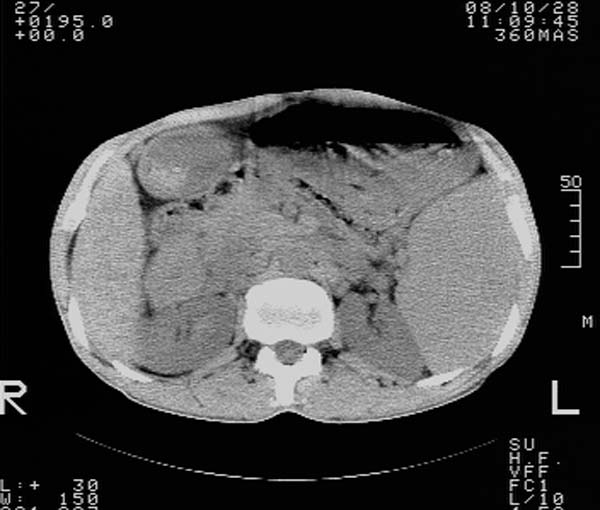

m,65y。半年前发现颈小结节,逐渐增多增大,现双侧耳后、颌下及颈部表浅淋巴肿大。胸片示双肺门增大。外院曾穿刺诊断为淋巴结核。在我科作胸腹部ct,我们觉得外院病检有误。现将图像上传请战友讨论。

纵隔内及腹膜后广泛淋巴结肿大,脾大,肝内似可见低密度影,结合病史半年前发现颈小结节,逐渐增多增大,现双侧耳后、颌下及颈部表浅淋巴肿大。考虑淋巴瘤。

我们也是首先考虑淋巴瘤。只是外院病检报告是结核。让人迷惑。肝左叶多发低密度占位,没增强不好定论。

纵隔,双肺门腹膜后多发淋巴结重大,非融合,肝脾轻度肿大,双肺野弥漫性小结节;考虑淋巴瘤,结节病可能性

纵隔内,双肺门、腋窝及腹膜后多发肿大淋巴结影,肺内小结节影,肝脾体积增大,支持淋巴瘤。肝内多发低密度影,考虑小囊肿。

纵隔内,双肺门、腹膜后多发肿大淋巴结影及颈部淋巴结肿大,肝脾体积大.结合临床,淋巴瘤可能性大。